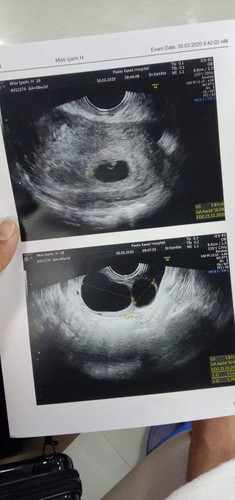

ตั้งครรภ์

สวัสดีค่ะพอดีเเม่บ้านนี้ไปฝากครรภ์ค่ะคุณหมอซาวพบตัวเด็กค่ะ เจอถุงซีสด้วยค่ะ 2ถุงไม่ทราบว่ามันมีความอันตรายต่อเด็กไหมค่ะ ตั้งครรภ์ได้ 6วีคค่ะ

รอซาวน์อีกรอบนะคะ บ้านนี้เจอน้องตอน8วีคค่ะ